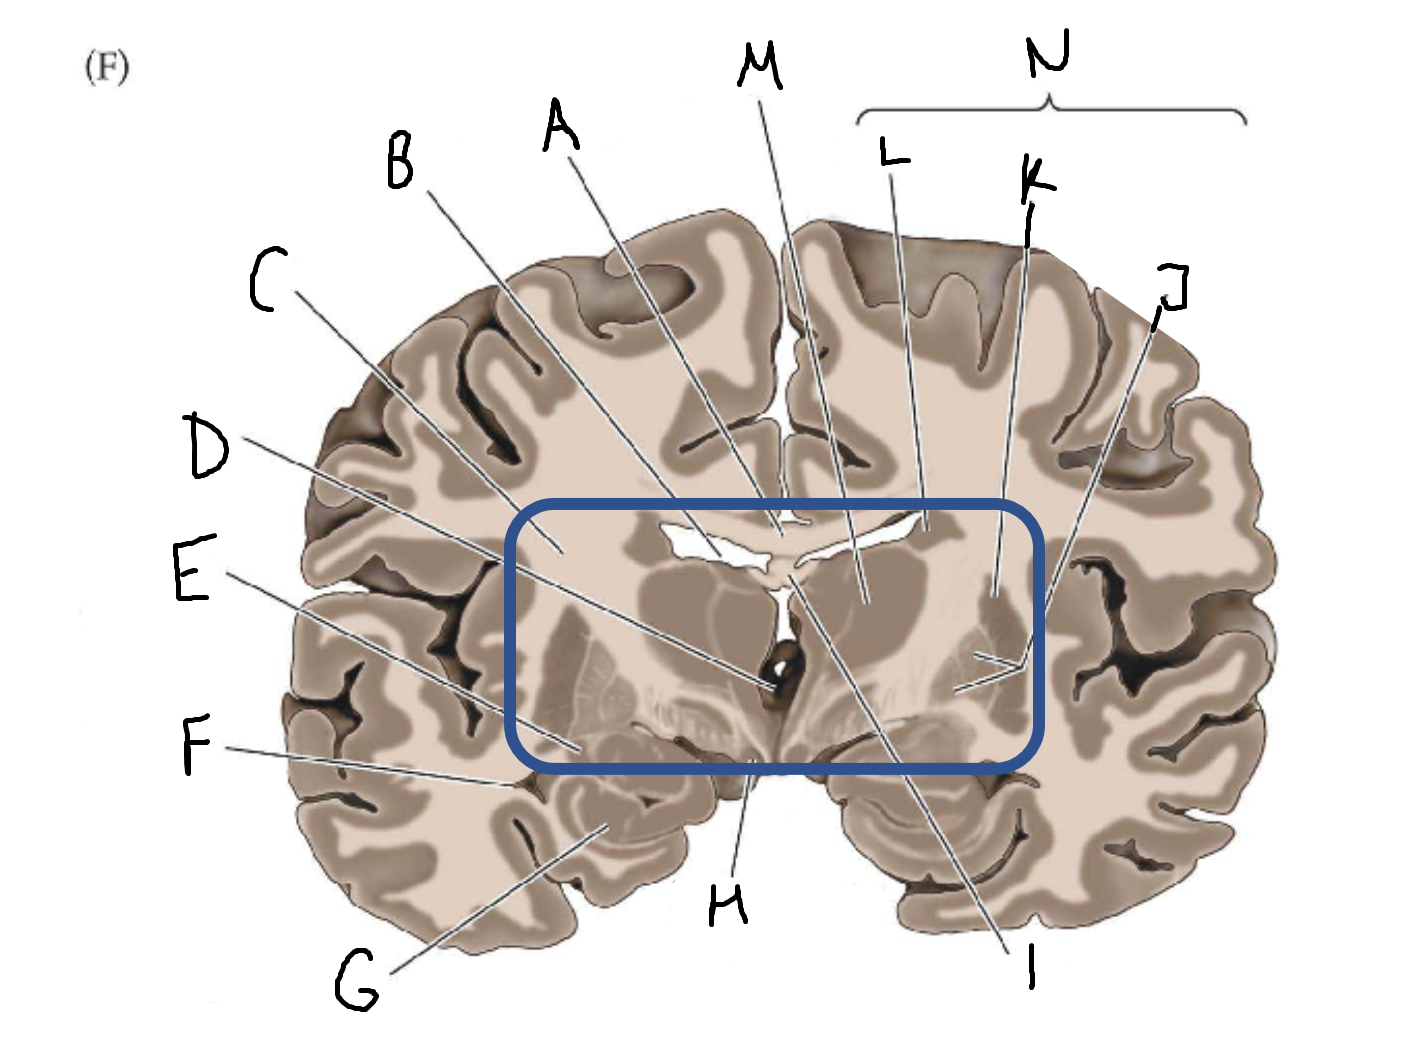

A

corpus callosum

B

lateral ventricle

C

internal capsule

D

third ventricle

E

tail of caudate nucleus

F

lateral ventricle

G

hippocampus

H

mammillary body

I

fornix

J

globus pallidus

K

putamen

L

caudate

M

thalamus

N

basal ganglia